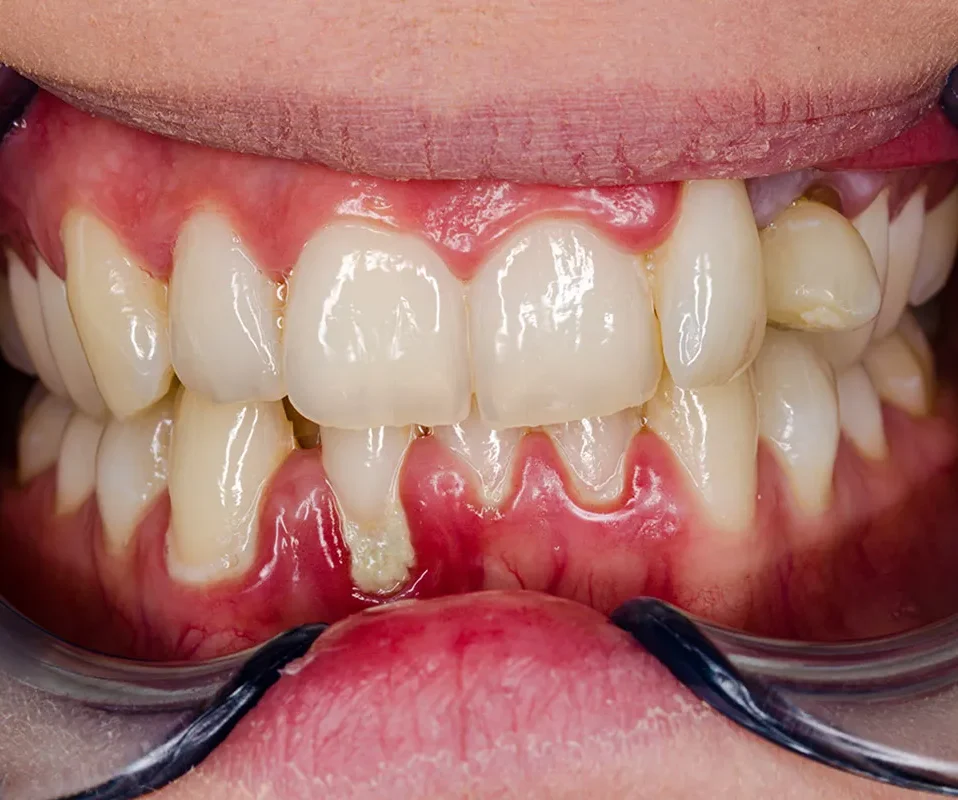

Gingivitis is a common gum disease characterized by inflammation and irritation of the gums, often caused...

Gum surgeries are dental procedures aimed at treating various gum-related issues, such as gum disease or gum...